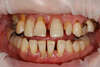

Ce patient présente la combinaison de plusieurs problèmes : infections, déchaussement dentaire, caries et dents absentes.

Après une phase d'assainissement et la mise en place de prothèses provisoires, une simulation en 3 dimensions de la situation est réalisée